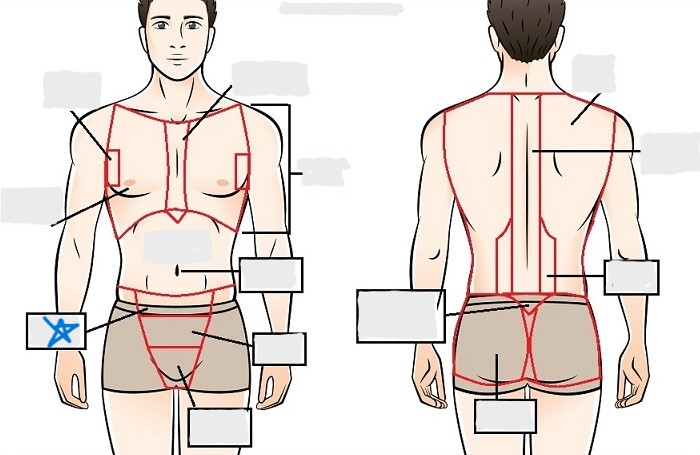

axial

cephalic

occipital

frontal

otic

orbital

nasal

oral

mental

cervical

dorsal

scapular

vertebral

lumbar

sacral

gluteal

thoracic

sternal

mammary

axillary

abdominal

umbilical

pelvic

inguinal

pubic

perineal

appendicular

acromial

brachial

antecubital

olecranal

antebrachial

carpal

manus

coxal

femoral

patellar

popliteal

crural

sural

peroneal

calcaneal

plantar